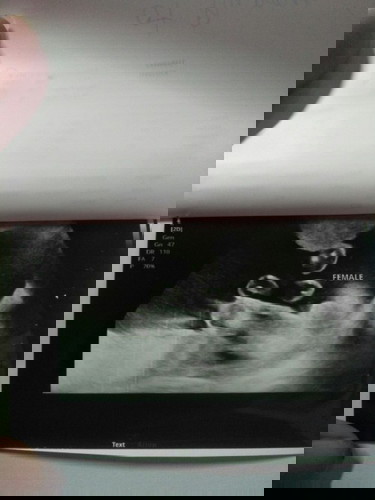

วันนี้23+2wแม่ไปอัลตราซาวนด์มาหมอบอกผู้หญิง100%จ้าแม่ดีใจมากพี่ชาย2คนแล้วคนที่3มาน้องสาวอิแม่ยิ้มหน้าบานปานกระด้ง ฟอร์ต ฟลุ๊ค เฟร์ญ่า